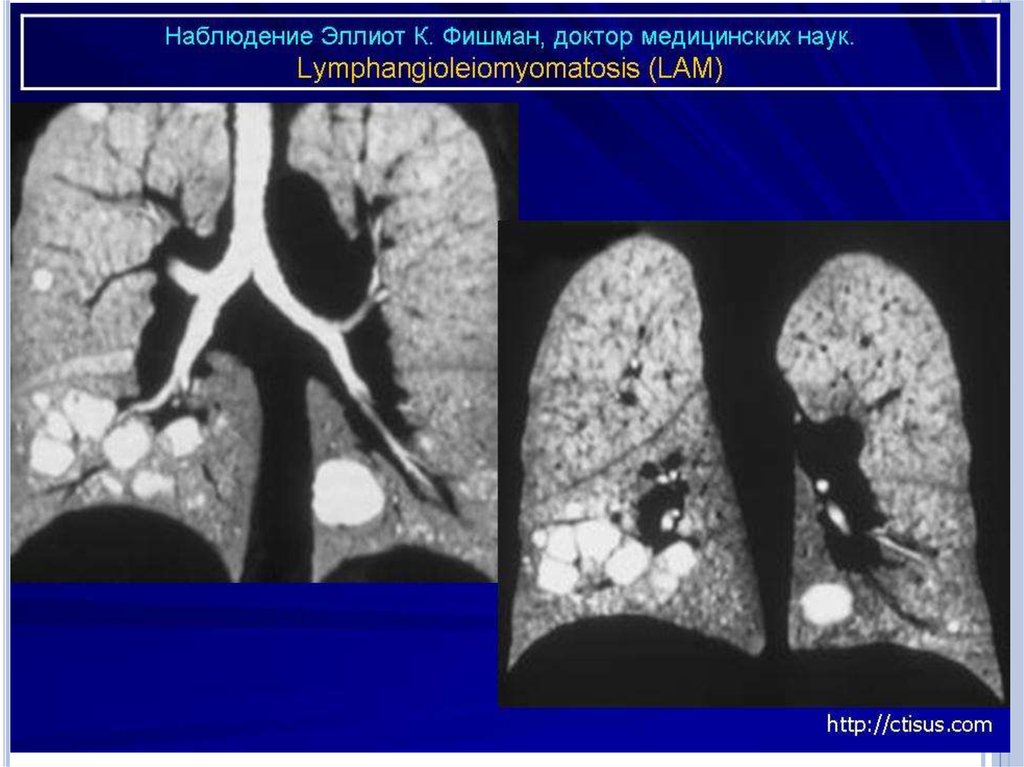

Инструментальные методы исследования

Рентгенологическое исследование легких - признаками

ЛАМ легких на обычных рентгенограммах грудной клетки

являются:

усиление легочного рисунка сетчатого характера;

увеличение объема легких.

Наиболее характерный морфологический признак ЛАМ кистозная трансформация легких, которая обычно выявляется

на компьютерных томограммах. Кисты бывают двух типов:

мелкие множественные типа «сотового легкого» и

крупные кисты, присущие буллезной эмфиземе.

Толщина стенки кисты не превышает 2 мм, причем стенка

кисты выявляется не всегда и не на всем протяжении.

Окружающая легочная ткань часто не изменена. Однако

сочетание фиброзных и кистозных изменений не

противоречит диагнозу ЛАМ. Таким образом,

рентгенологическая картина ЛАМ не патогномонична.

Ведущим рентгенологическим признаком этого заболевания

является образование множественных воздушных

11.

Компьютерная томография легких. Для ЛАМ

характерны множественные диффузные, хорошо очерченные

мелкие тонкостенные кисты. Кисты при этом заболевании

значительно отличаются от зон центрилобулярной эмфиземы

легких, которые не имеют четких границ и своих собственных

стенок, а также от фиброзирующего альвеолита, при котором

основные изменения расположены по периферии легких,

имеются поля фиброза и дезорганизации паренхимы легких,

а кисты расположены субплеврально и

характеризуются довольно толстыми стенками.

Данные компьютерной томографии настолько специфичны

для ЛАМ, что некоторые авторы для постановки точного

диагноза полагают достаточным заключение компьютерной

томографии (КТ) без проведения биопсии легких.